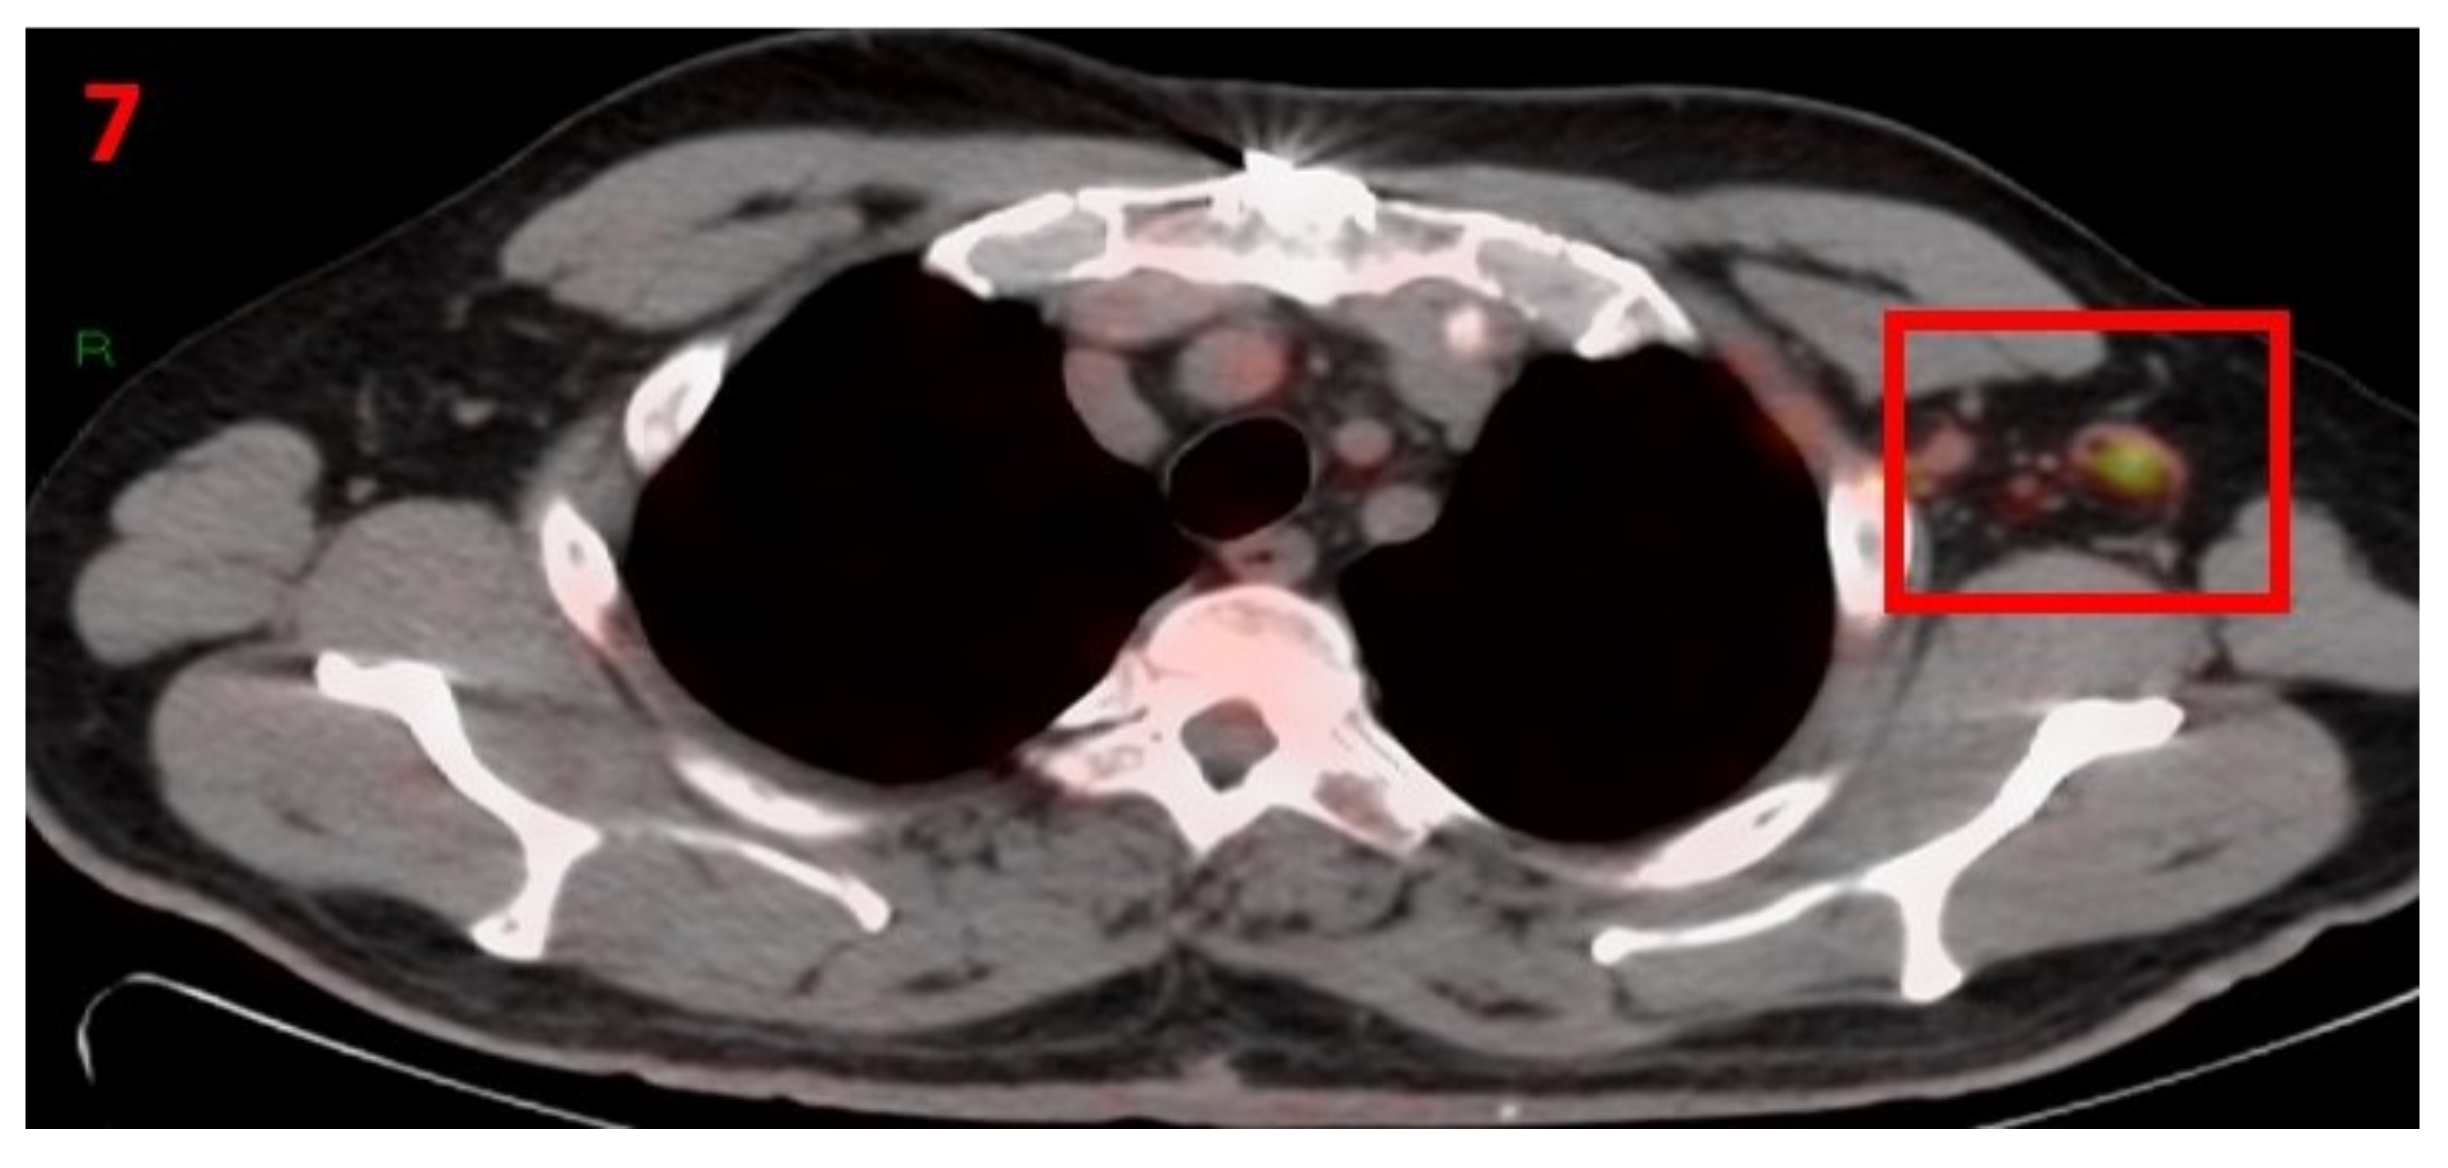

3.7. Case No 7

| Case no.7 | Gastric lymphoma | Left arm | 6 days | Hypermetabolic uptake in the left axillary region and lymphadenopathy | Second vaccine | 10 mm | 3 | Pfizer-BioNTech |